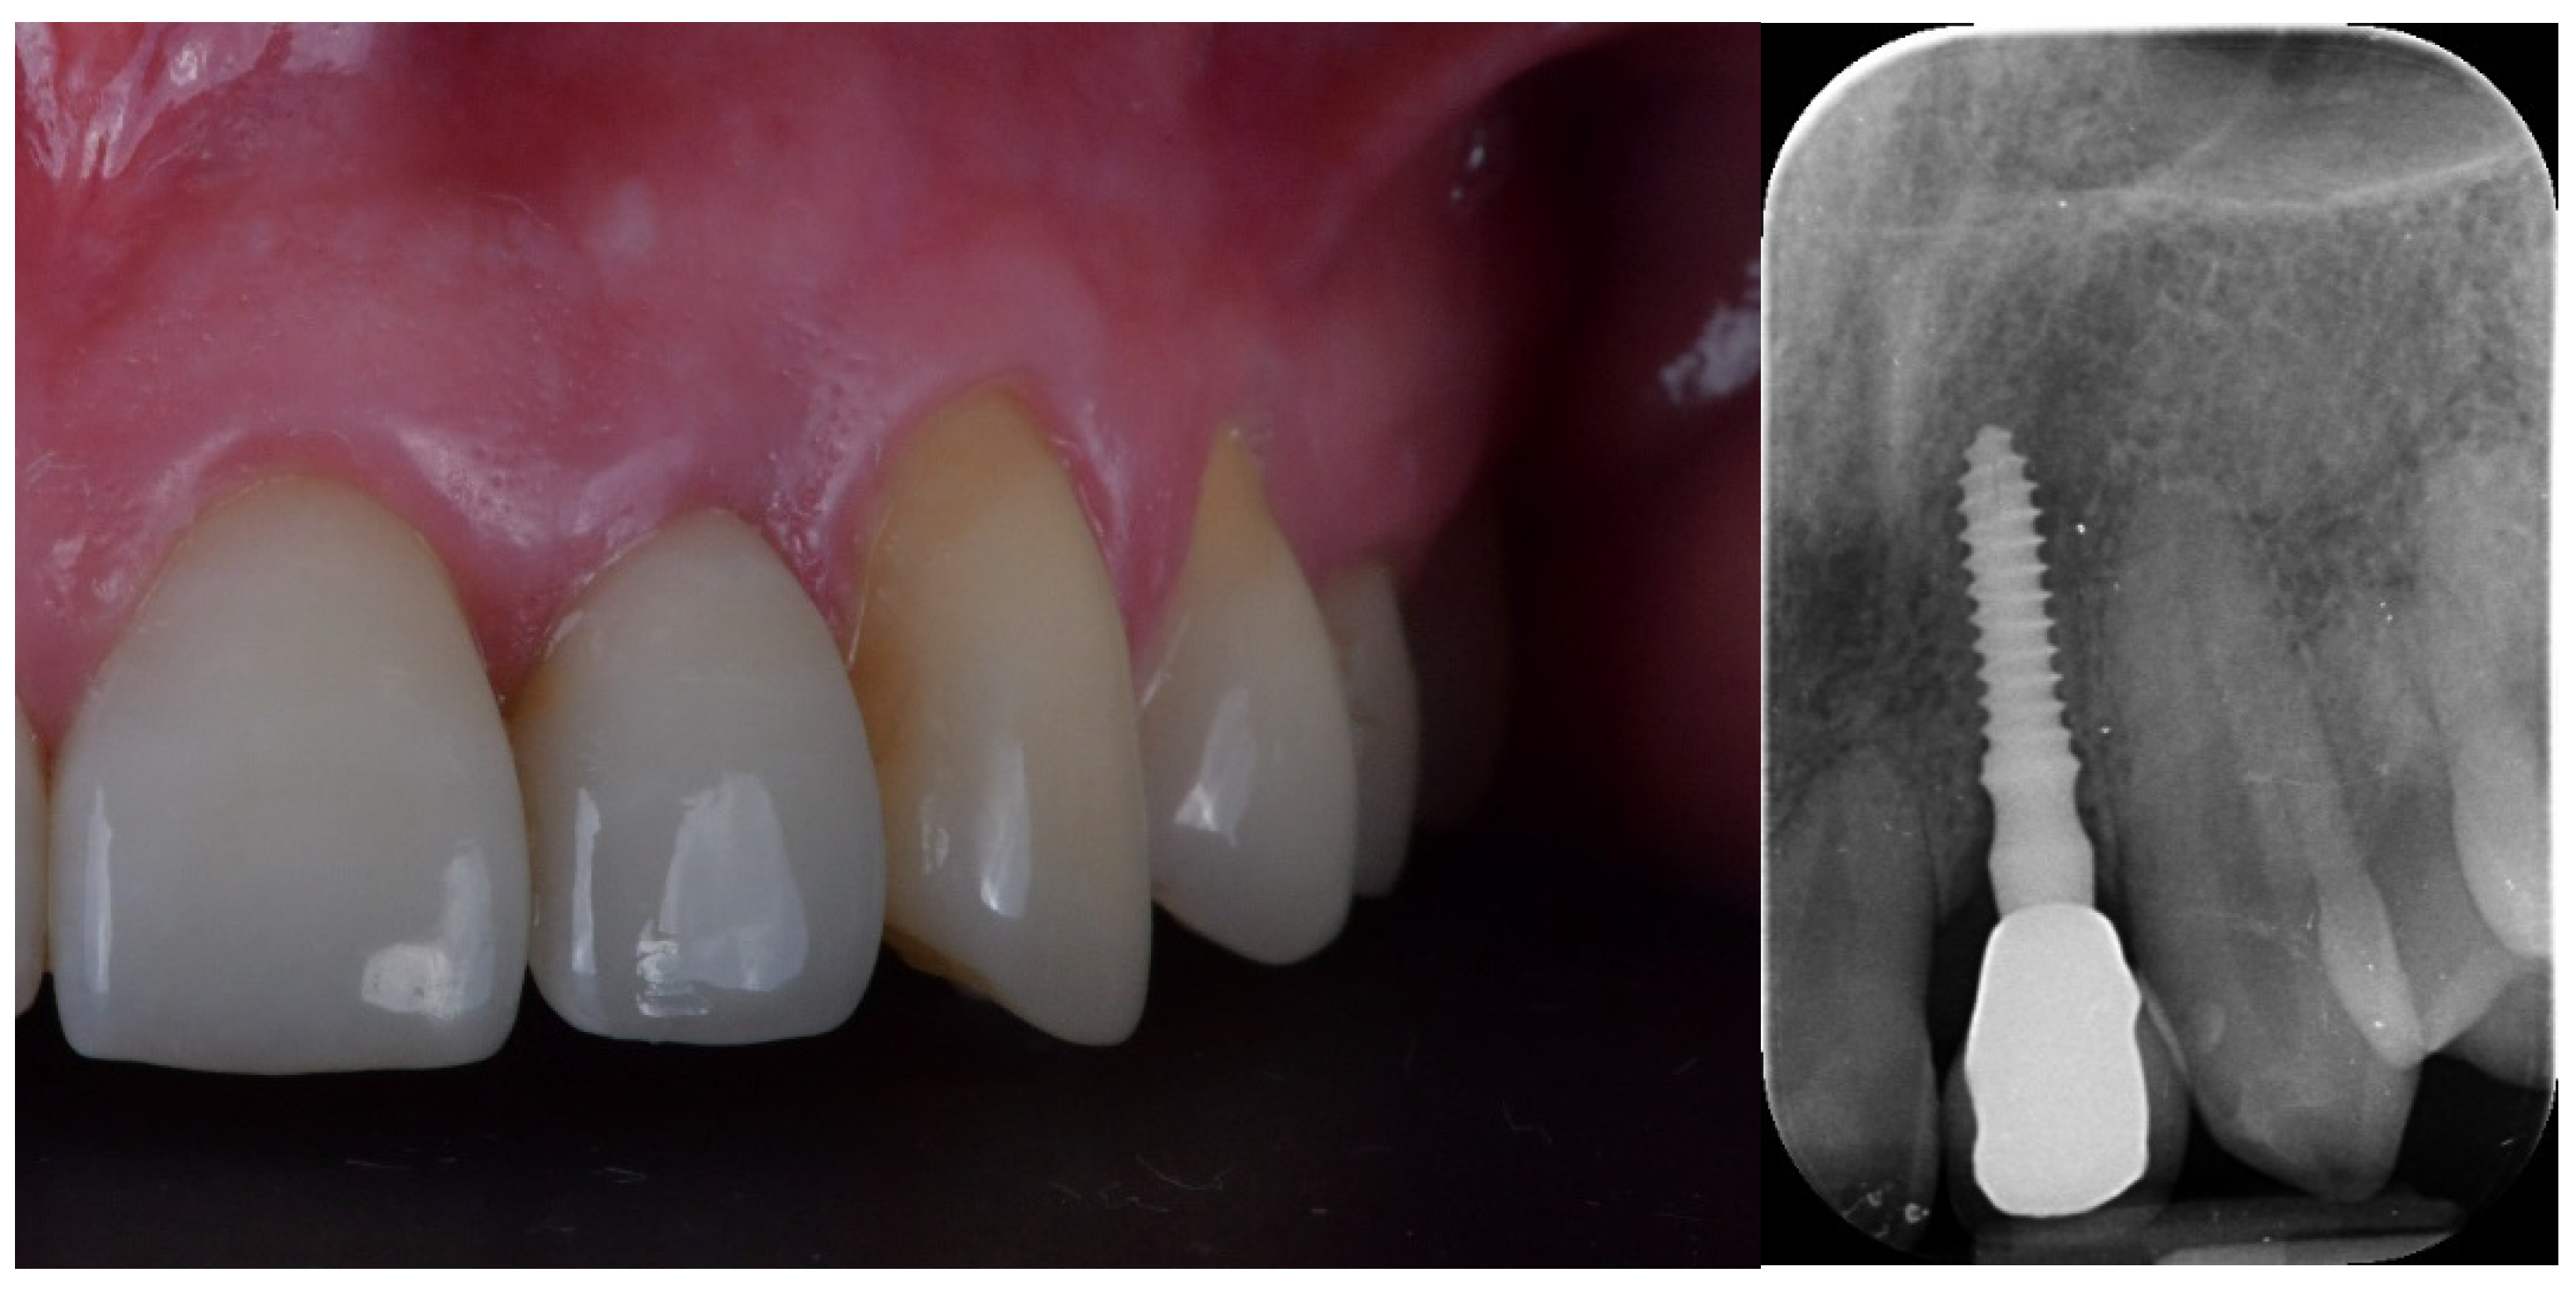

- Esthetic evaluation of clinical pictures, including at least two adjacent teeth, taken at two years after loading was done following the pink esthetic score (PES) proposed by Fürhauser et al., in 2005 [31]. In brief, the PES score evaluates seven variables: mesial papilla, distal papilla, soft tissue level, soft tissue contour, alveolar process deficiencies, soft tissue color and texture. A 0-1-2 scoring system was used, with a maximum achievable score of 14 per site.

| PES 3 at the 2-year follow-up | 12.6 ± 0.97 | 12.2 ± 0.92 | 0.3554 |